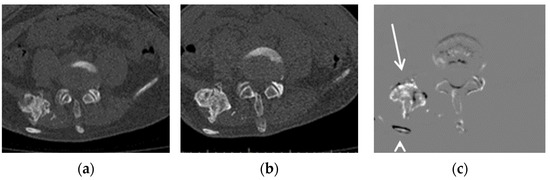

Figure 2.

Example of a growing lesion. CT images of a 16-year-old FOP patient: (a) previous CT image, (b) current CT image, and (c) TS (subtraction) image. The growing lesion near the ilium (arrow) is difficult to detect in the current CT image, but is clearly visible in the TS image. The dorsal rib of this lesion (arrowhead) is shown due to misregistration.